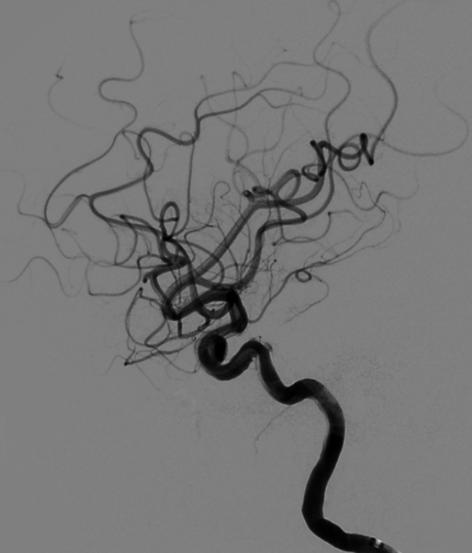

入院后行DSA检查明确右侧颈内动脉眼动脉后下方囊状动脉瘤样影,大小约1.09mm×6.53mm,宽基底,其下方见两个小囊状突起,左侧颈内动脉眼动脉后方及虹吸段均可见小囊状突起。考虑颅内多发动脉瘤。

麻醉成功后,患者仰卧,常规消毒,铺巾, Seldinger法穿刺右侧股动脉,置入5F动脉鞘,置入5F造影管行右侧颈内动脉正侧位及3D造影后,更换6F长动脉鞘,6F中间导管在导丝引导下进入右侧颈动脉分叉端并固定。根据3D造影选择工作体位并放大做路图后,T-track微导管在微导丝引导下进入右侧大脑中动脉,经微导管送入4.0×45mm Tubridge®支架,观察 Marker位置后,于颈动脉分叉附近缓慢释放支架。

全脑DSA正侧位造影示血流通畅。